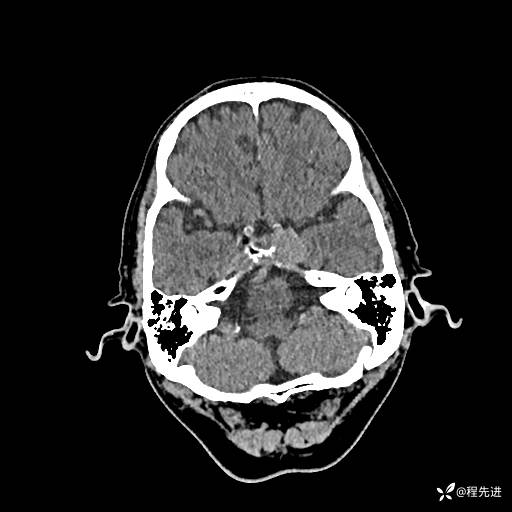

患者性别:男

患者年龄:74岁

简要病史:出现视物重影2月余,未予重视,2月来症状逐渐加重

实验室检查:无特殊

CT平扫: